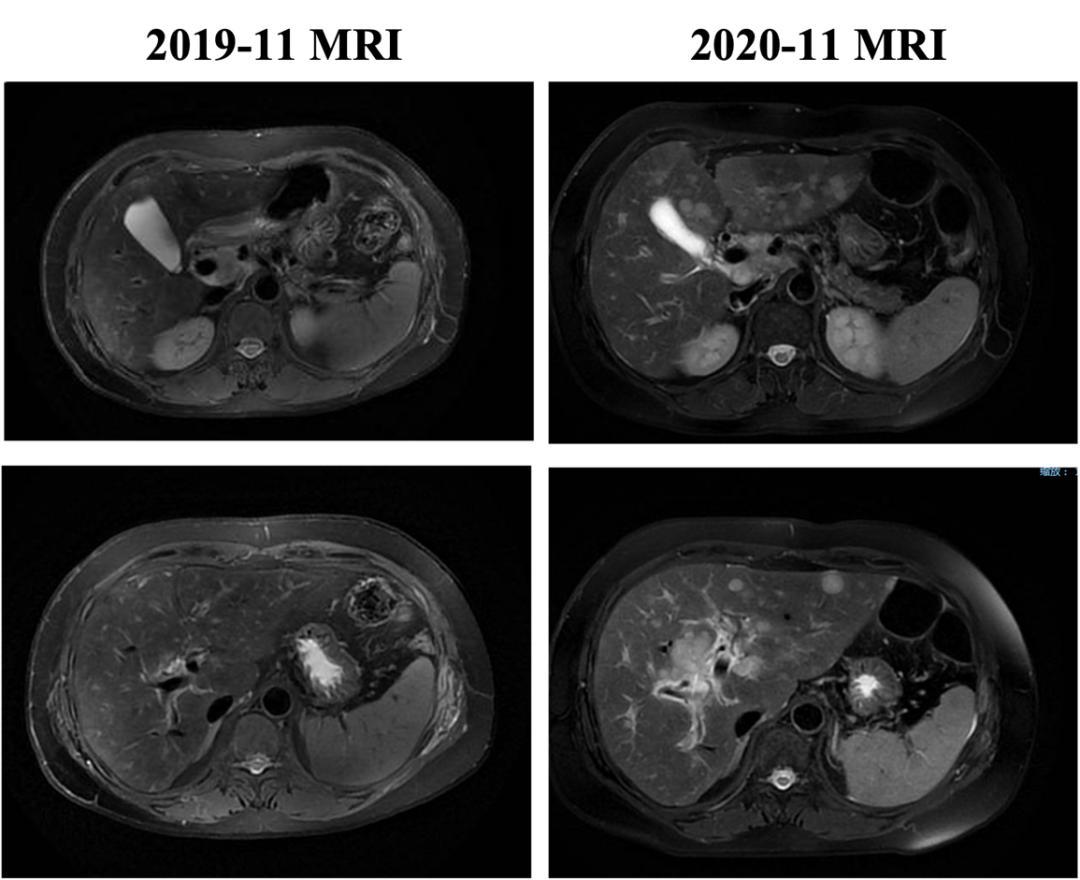

2019-11开始换用吡咯替尼联合长春瑞滨治疗,最佳评效:SD。2020-11新发肝转移病灶,评效PD,PFS为12月。不良反应:腹泻1-2级,手足麻木级(期间因不良反应予吡咯替尼减量,长春瑞滨改节拍减量)。

图5. 四线治疗

▌五线治疗:

自2020-11-10行白蛋白紫杉醇+伊尼妥单抗治疗2周期,具体:伊尼妥单抗8mg/kg 首剂,6mg/kg 后续d1+白蛋白紫杉醇125mg/m2 200mg d1、d8,Q21d。2周期后肝转移增多、增大,肝门区及门腔间隙肿大淋巴结部分缩小,综合评效PD,PFS为1.5月。

图6. 五线治疗